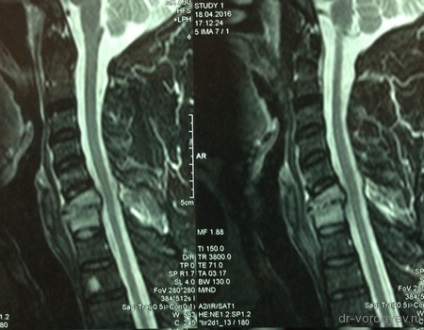

Pacientul sa plâns de dureri la nivelul coloanei vertebrale cervicale care radiază brațele. El a fost tratat într-un spital neurologic, în cazul în care RMN-ul a aratat inflamatie a vertebrelor.

Doar după terapia cu antibiotice masive, pacientul a suferit o intervenție chirurgicală: corporectomy C6, C7. Cage Corporodesis alunecare (corp vertebral protetice) ADD + Ulrich, Germania și înlocuitor de os de corali. Pe CT de control în picioare implanturi decompresie corectă, adecvată.